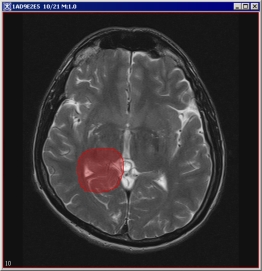

Evaluate Segmentation

Evaluate Segmentation operation compares segmentation results of a test image to segmentation results of an ideal gold standard true image. For each evaluated segmentation pair, the false negative volume fraction, the false positive volume fraction, and the positive volume fraction are sent to the Output window. See Figure 13)-e.

When the algorithm finishes running, the result statistics appears in the Output window. See also Figure 13.

Figure 13. The Evaluate Segmentation algorithm : (a) - a gold standard segmented image, (b) - its unsigned byte mask, (c) - a segmented image for evaluation, (d) - its unsigned byte mask, and (d) - the Evaluate Segmentation dialog box and the Output window